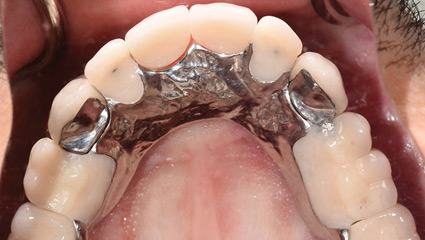

The Strategic Use of Compromised Teeth/Tooth Roots to Help Serve as Abutments for a Fixed Provisional Prosthesis During Implant Reconstruction

Convenient Engineering’, a term coined by Michael Cohen ‘Interdisciplinary Treatment Planning, Quint Dec. 2011’, states that “while planning cases on ‘auto-pilot’ may save time and money and may be compatible with both the wishes of the dentist and the patient, it may also be thought of as ‘CONVENIENT ENGINEERING’ and is not necessarily in the … Read more